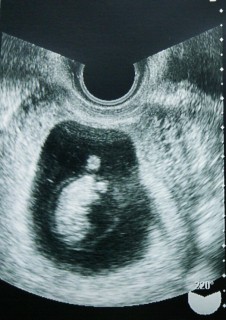

切迫流産との診断を受け、1ヶ月寝たきりの生活を送ってました。 5日ぶりに検診に行ったら、さらっと「双子だよ~」って言われてびっくり!! 一卵性の双子でした!! 2つの心臓がちゃんと動いているのが見えて感動~!! どうかこのまま順調に育ってうまれてきますように!!